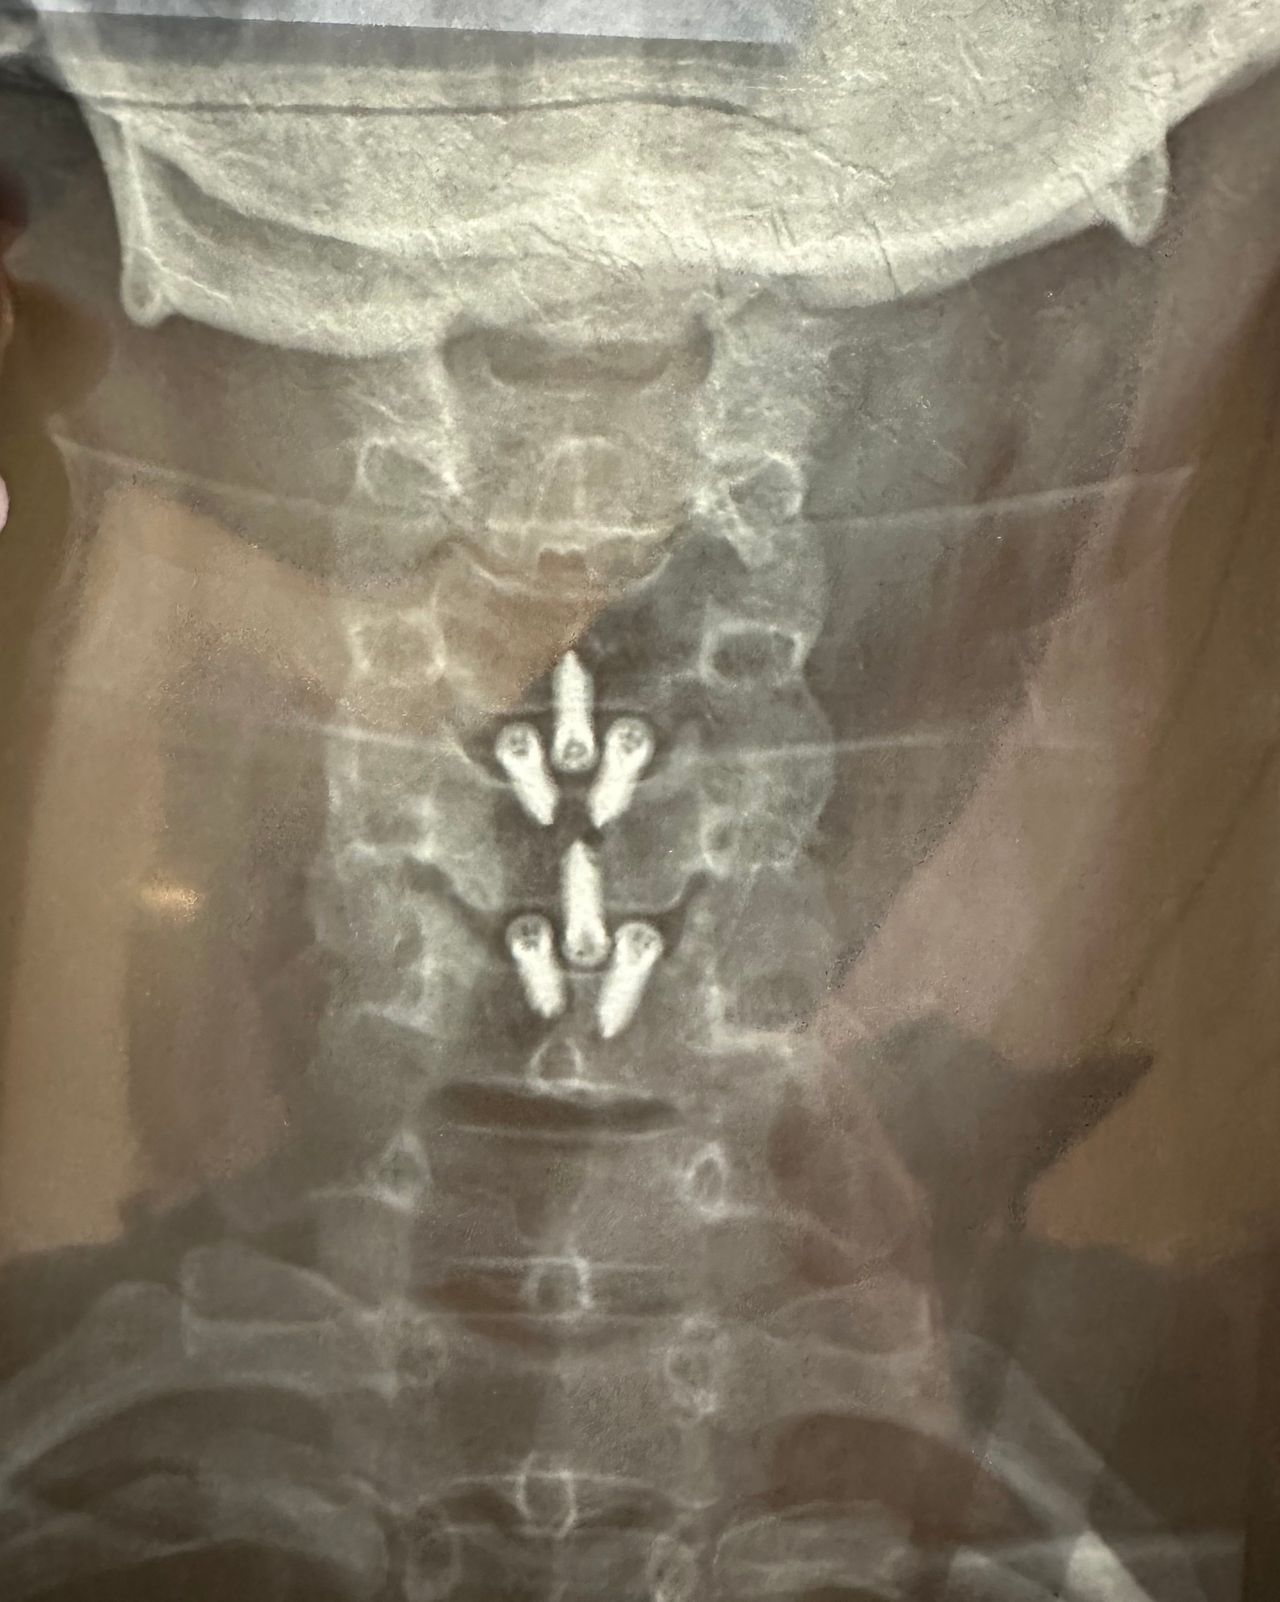

- Chirurgia Mininvasiva percutanea vertebrale - stabilizzazioni e artrodesi intersomatiche (per fratture vertebrali, spondilolistesi, instabilità vertebrali, discopatie)

- RX scopia intraoperatoria